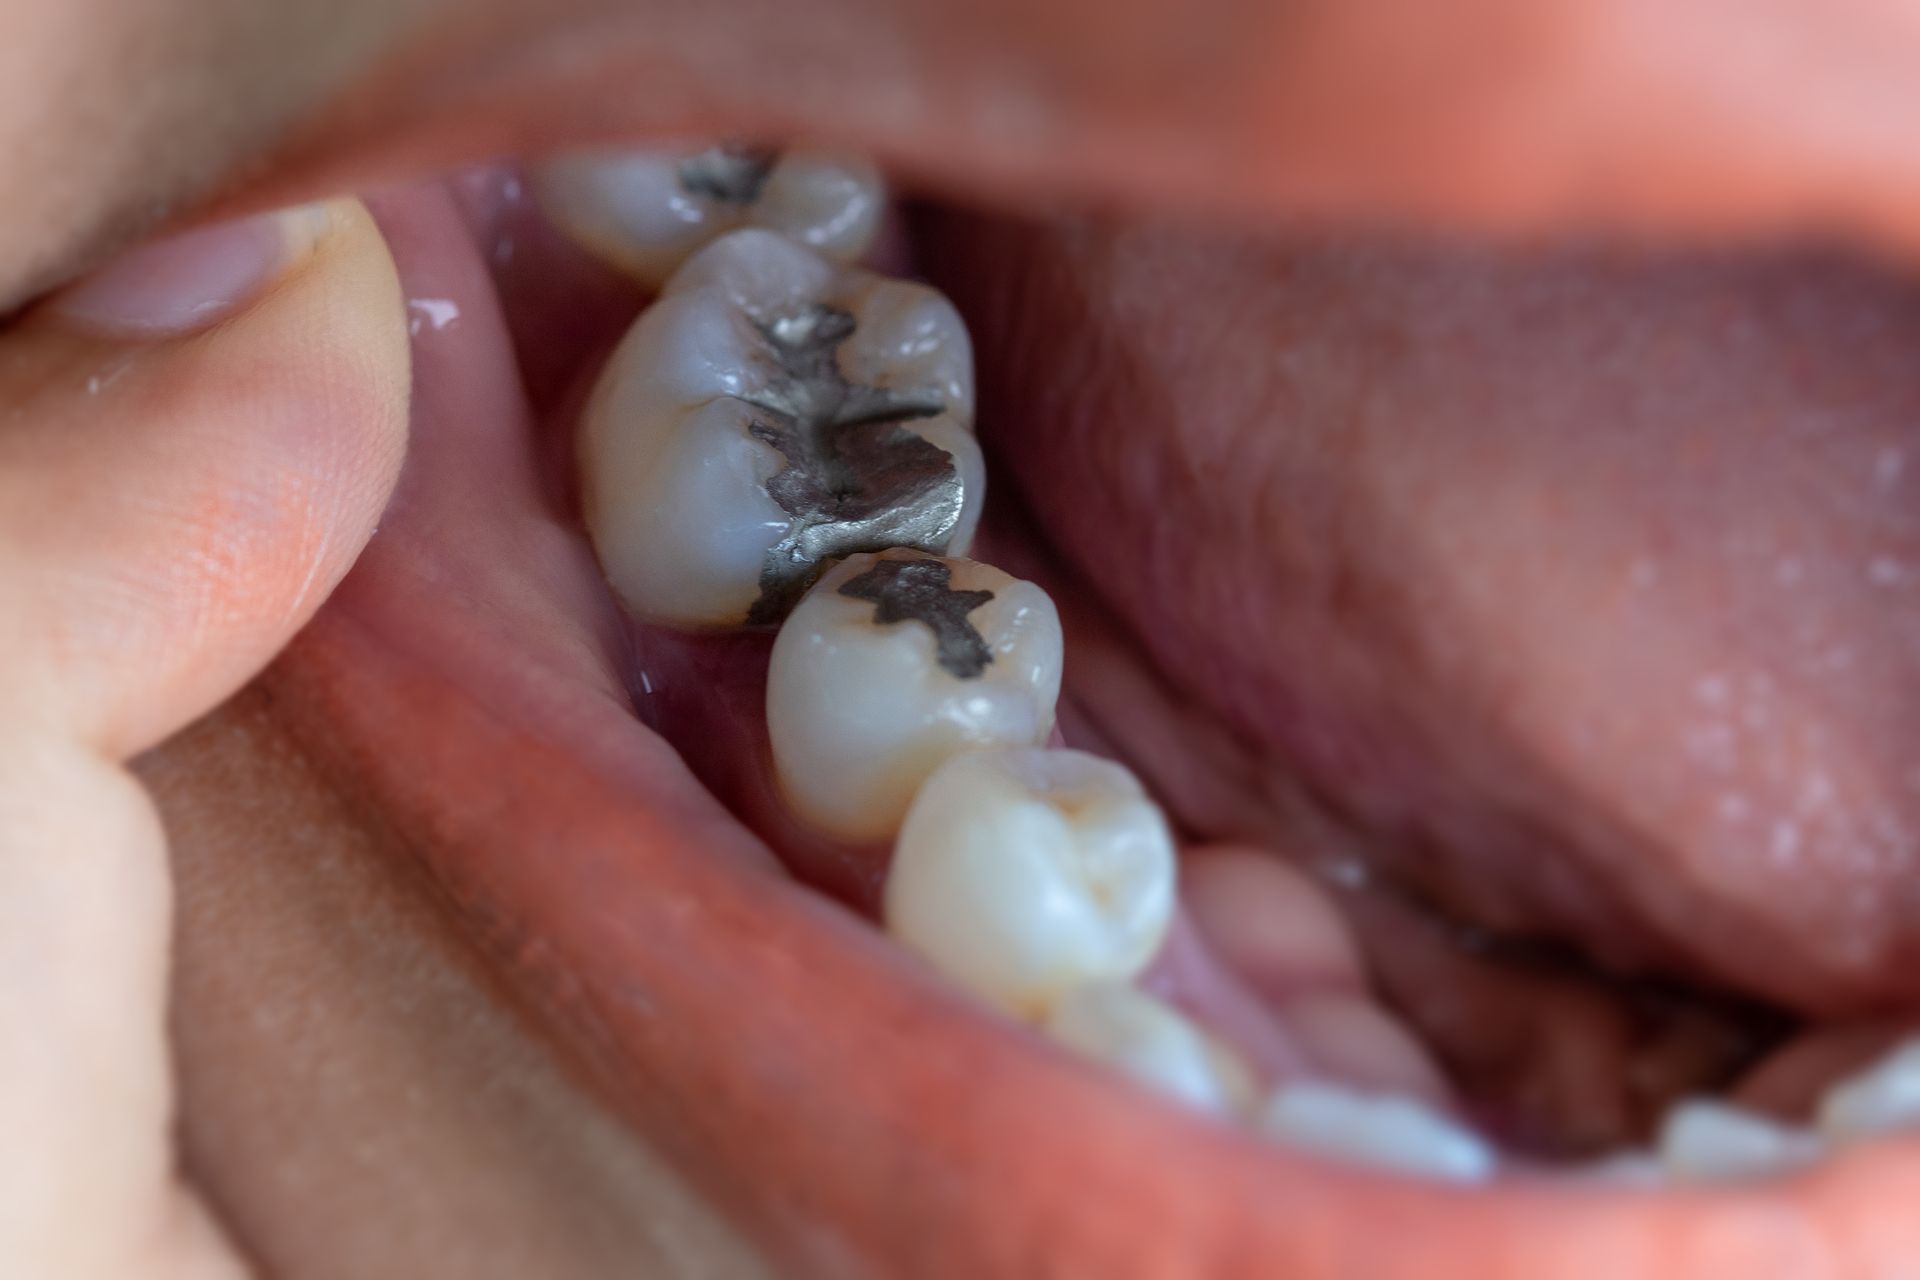

Dentisterie opératoire (plombage)

Cette branche de la

médecine dentaire consiste à enlever les tissus durs affectés par la maladie infectieuse qu’est la carie et remplacer la partie manquante par une obturation - en d’autres mots, faire un plombage. Les obturations en composite (plombages blancs) sont les plus populaires, malgré que certaines situations requièrent l’utilisation de l’amalgame (plombage gris).